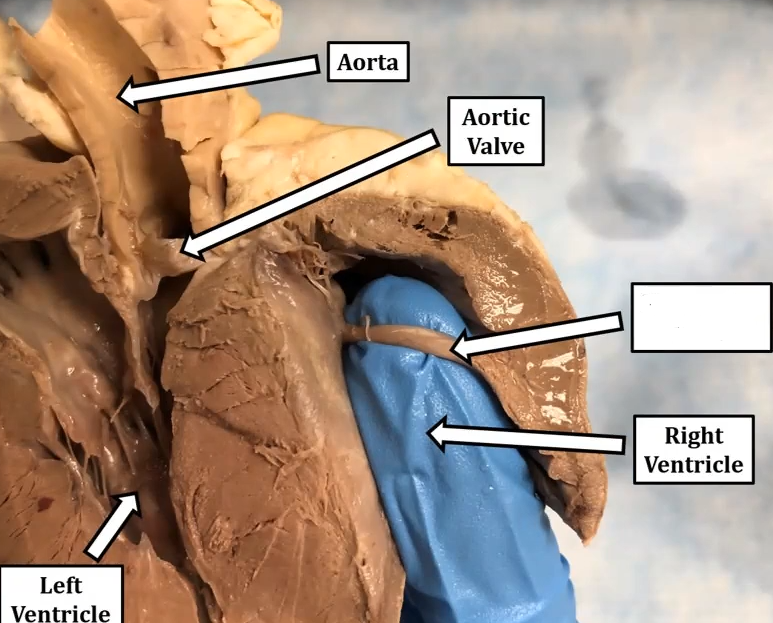

3. left atriumright ventricle

interventricular septum

left ventricle